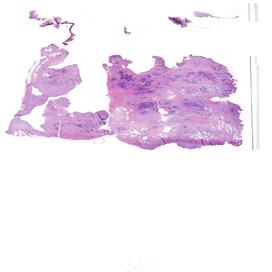

Il carcinoma sieroso ad alto grado dell’ovaio rappresenta una delle neoplasie ginecologiche più aggressive, con un alto tasso di recidiva e una sopravvivenza a lungo termine ancora limitata, nonostante i progressi terapeutici degli ultimi anni. I biomarcatori predittivi di risposta al trattamento, tra cui l’espressione del recettore dei folati (FRα), stanno emergendo come strumenti essenziali per personalizzare le terapie e migliorare gli esiti clinici delle pazienti. Il progetto nasce con l’intento di promuovere un apprendimento interattivo, coinvolgendo i partecipanti in attività mirate al miglioramento dei processi diagnostici e operativi. I patologi, infatti, rivestono un ruolo fondamentale nell’identificazione e caratterizzazione dei biomarcatori predittivi, contribuendo all’ottimizzazione dei percorsi terapeutici. L’evento, strutturato in due incontri online, si pone come obiettivo quello di fornire ai partecipanti gli strumenti teorici e pratici per l’esecuzione, la valutazione e l’interpretazione dei test di espressione dei biomarcatori. L’intento è quello di promuovere un approccio diagnostico sempre più integrato e personalizzato, ponendo l’accento sull’importanza di mantenere standard qualitativi elevati e monitorare nel tempo il proprio lavoro. Per raggiungere questo obiettivo formativo verranno messi a disposizione dei partecipanti kit specifici per esercitarsi nel perseguire la qualità e verificarla nel tempo. I risultati verranno poi discussi nella puntata finale del percorso.

OVAIO

2025 B 01348 A1 EE